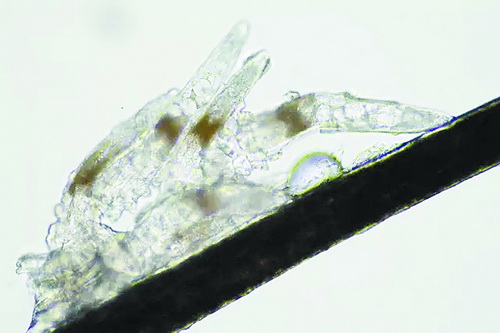

顯微鏡下長(zhǎng)在睫毛中的螨蟲

冬天來了,氣溫降低,睫毛上的“隱形殺手”蠕形螨卻沒有要冬眠的意思。廈門大學(xué)附屬廈門眼科中心11月初開設(shè)蠕蟲性瞼緣炎門診以來,每天來查螨的市民都特別多,短短一個(gè)多月,已有近千人在顯微鏡下見到長(zhǎng)期寄居在自己睫毛上,朝夕相處,卻素未謀面的蠕形螨。